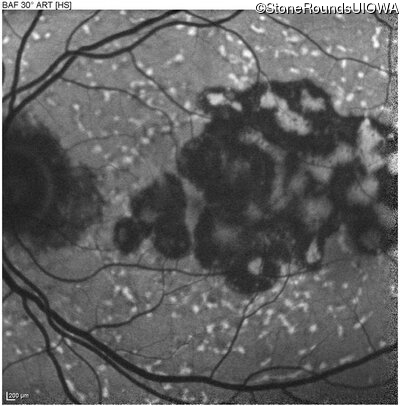

AR Stargardt Disease (IIA)

Age at visit: 59 years

This 59 year old man has noticed some blank spots near the center of his vision over the last 2 years.

AR Stargardt Disease ABCA4 Leu2027Phe CTC>TTC IVS30+1321 A>G AR